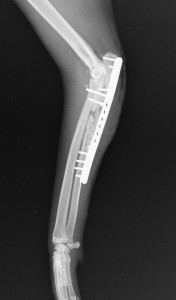

症例は推定12~13歳齢の日本猫。1か月程前にタンスから落下し、左前足を着かなくなり、他院にて骨折の手術を受けたが経過が良くないとの事で来院しました。以下が初診時のレントゲン所見です。

左前肢は尺骨の骨折と橈骨脱臼が併発した、モンテジア骨折を起こしていました。それをプレートとスクリュー、ワイヤー、そしてギプスにより固定が試みられていましたが、骨癒合はほぼ進んでおらず、肘に近い位置のスクリューは既に抜けかかっていました。

また、骨折部は不適切に固定されたために掌側面(手のひら)が180度回転した状態で固定がされていました。(下画像の矢印部分)